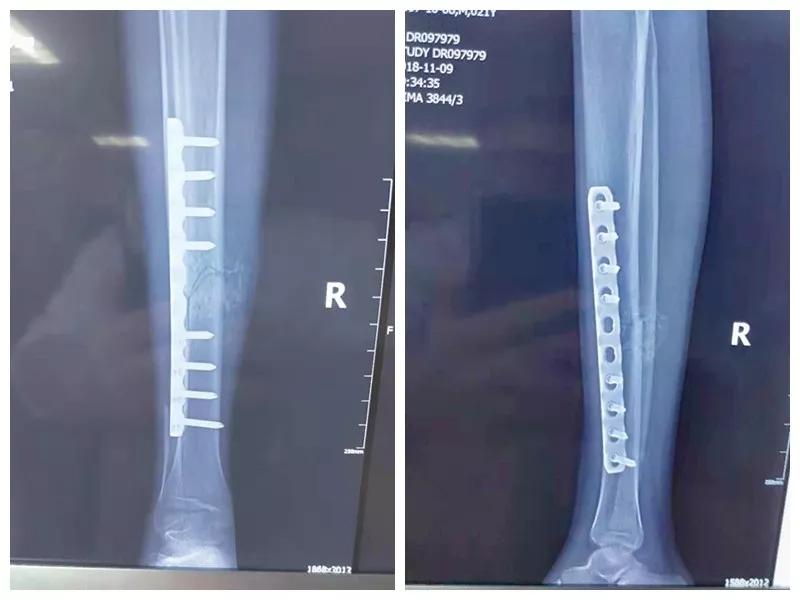

这名21岁的男性患者一个月前因车祸致伤,在当地某三甲医院确诊为右胫腓骨粉碎性骨折,骨折移位明显,建议手术治疗,因既往患严重慢性再生障碍性贫血病史16年,一般状况差,需长期输注血液制品维持三系细胞水平,麻醉及手术风险极高。虽经当地积极内科治疗,患者一般状况仍差,无法耐受手术治疗。患者及家属经多方打听,抱着最后一丝希望来到我院骨二科求治。

骨二科张延平主任接诊后经仔细询问病史,详细阅读近期X线、CT等病历资料,认为患者骨折移位明显,目前骨折无任何愈合迹象,若保守治疗,骨折将无法愈合,后期不能下地活动,严重影响患者生活质量。同时患者合并慢性再障,血常规结果各项指标均极低,围术期发生麻醉意外、大出血、感染等风险极高;而我院作为西安市级最大的三甲综合医院,综合实力深厚,既往相关疾病治疗经验丰富,多次通过多学科诊治为合并复杂内科疾病患者保驾护航,为患者创造手术时机,提高患者生活质量,遂将患者收住院。住院后,立即成立了由张延平主任、杨寅副主任、山卉护士长、梁晨主治医师、刘邦定主治医师、李鑫护师组成的手术治疗小组。经初步检查,患者血常规结果较当地检验结果更差,三系细胞均极低,其中血小板仅为1(正常值为100-300),血红蛋白55g/L。遂立即请血研所李罡灿主任医师会诊,给予升高白细胞、纠正贫血、升高血小板等治疗,经积极治疗患者血常规各项指标均较入院时改善。张延平主任再次组织由血研所李罡灿主任医师、麻醉科崔晓岗主任、感染科付建军主任、药剂科韩小年副主任药师等参加的术前讨论。讨论后一致认为患者目前各项指标虽然较入院时改善,但因其慢性再障病史长,骨髓造血及储备能力极差,围术期发生大出血、伤口感染甚至全身感染等风险仍极高,术中及术后需准备大量血小板防止大出血,同时需高度警惕手术切口、取骨区术后发生感染。为尽快为患者施行手术,治疗小组积极联系输血科为患者备血,并为患者制定了围术期抗感染方案;在我院输血科存血量严重不足的状态时,输血科张养民主任亲自联系市中心血站为患者准备手术中及术后所需的血小板制品。手术小组为患者制定了周密的手术方案及风险预案,10月31日,在麻醉科王永宏副主任医师、手术室高洁、赵耀护师的配合下,为患者施行了右胫骨粉碎性骨折切开复位、髂骨取骨植骨内固定术,手术历时70分钟,安全返回病房。术后患者渗血多,1周内连续每日平均渗血超过100ml,并出现发烧,最高39℃,复查血常规三系细胞较术前再次明显降低。李罡灿主任医师、付建军主任、韩小年副主任药师多次来科会诊,及时调整患者的治疗方案,输血科再次为患者的救治提供了强有力的支援和保障。在山卉护士长带领的护理团队精心护理下,患者未发生压疮等卧床并发症。目前该患者术后恢复良好,已出院进行下一步康复治疗。